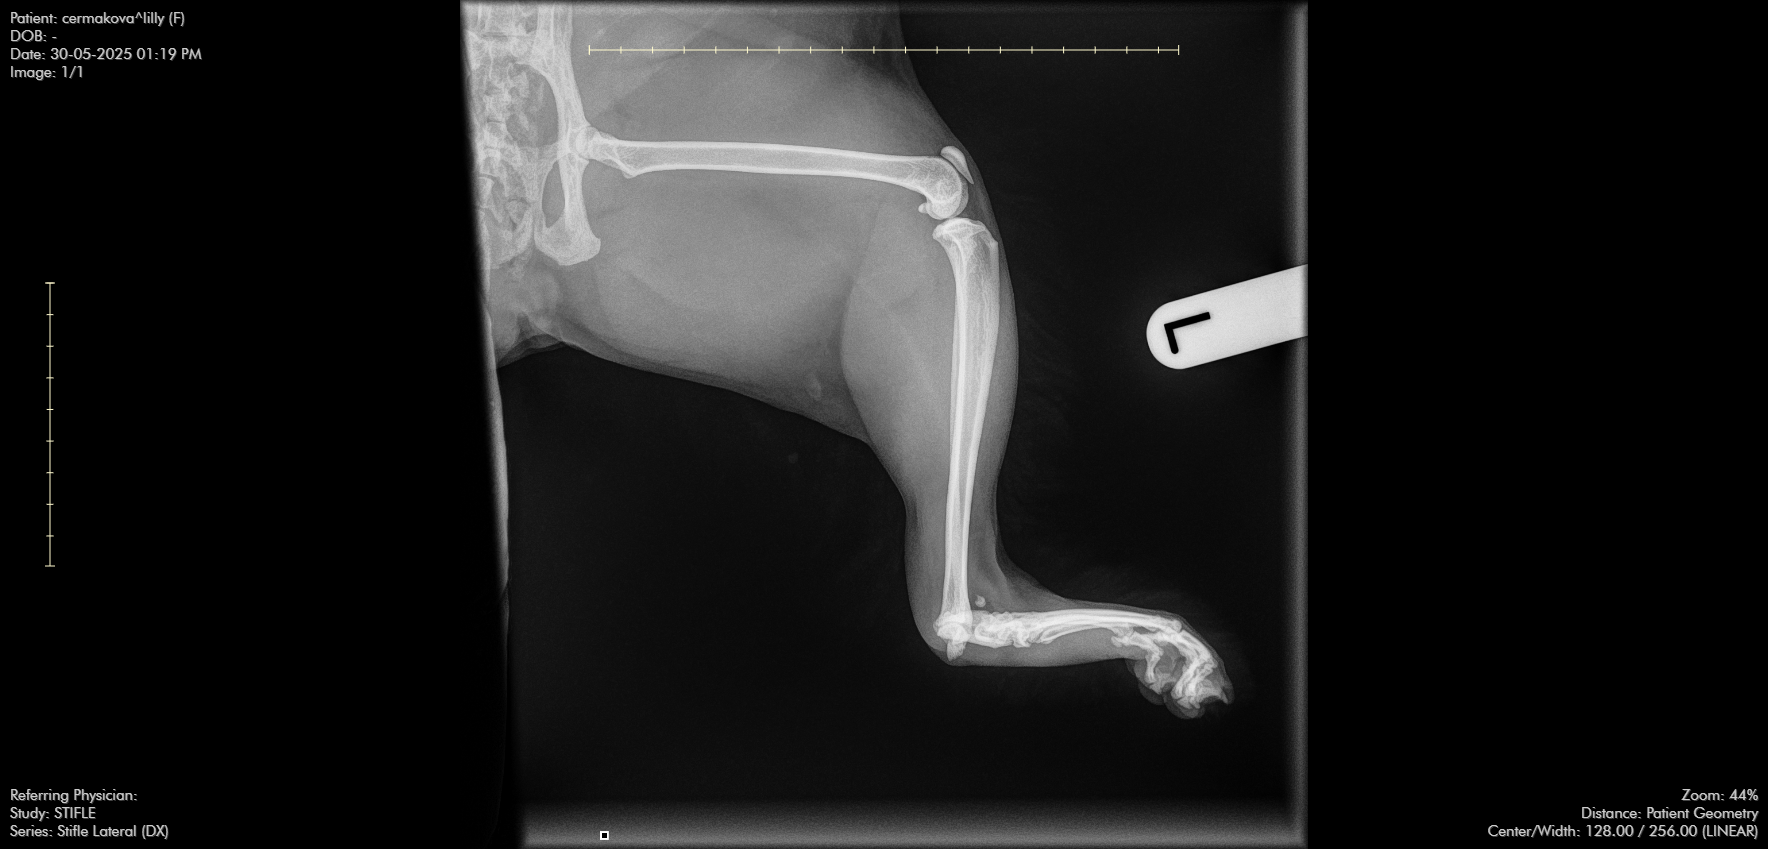

She slipped through the door and jumped out of a window, which resulted in a fractured tarsal bone.

At first, the outlook was devastating — I was told amputation might be the only option. But then I found out that surgery can fix it. I was so relieved — until I learned the cost. The surgery could cost up to £10,000 because the fracture is in a very complicated location.